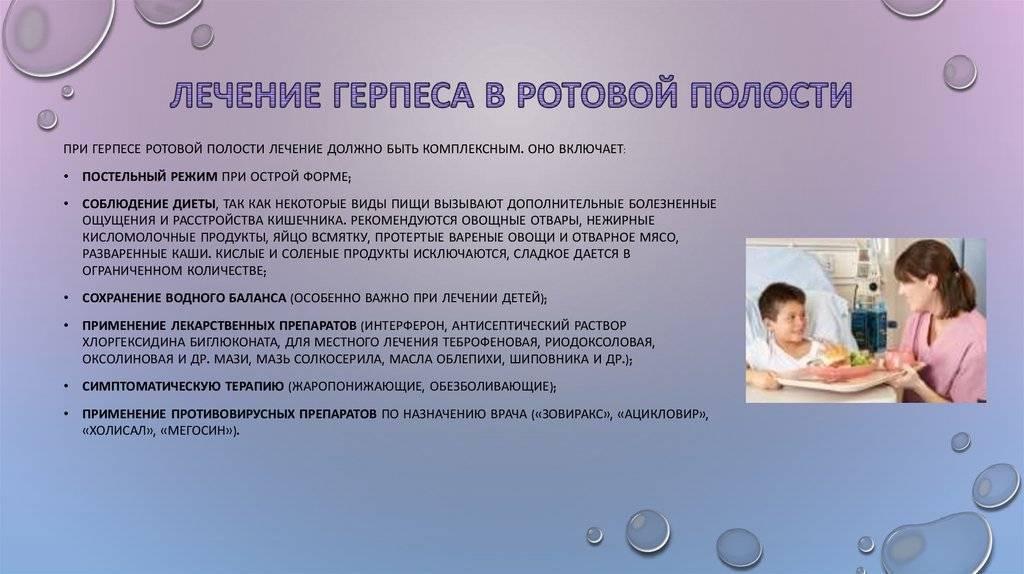

Медицинские снимки и изображения опоясывающего герпес вируса

Раздел: Фотодневник открытий